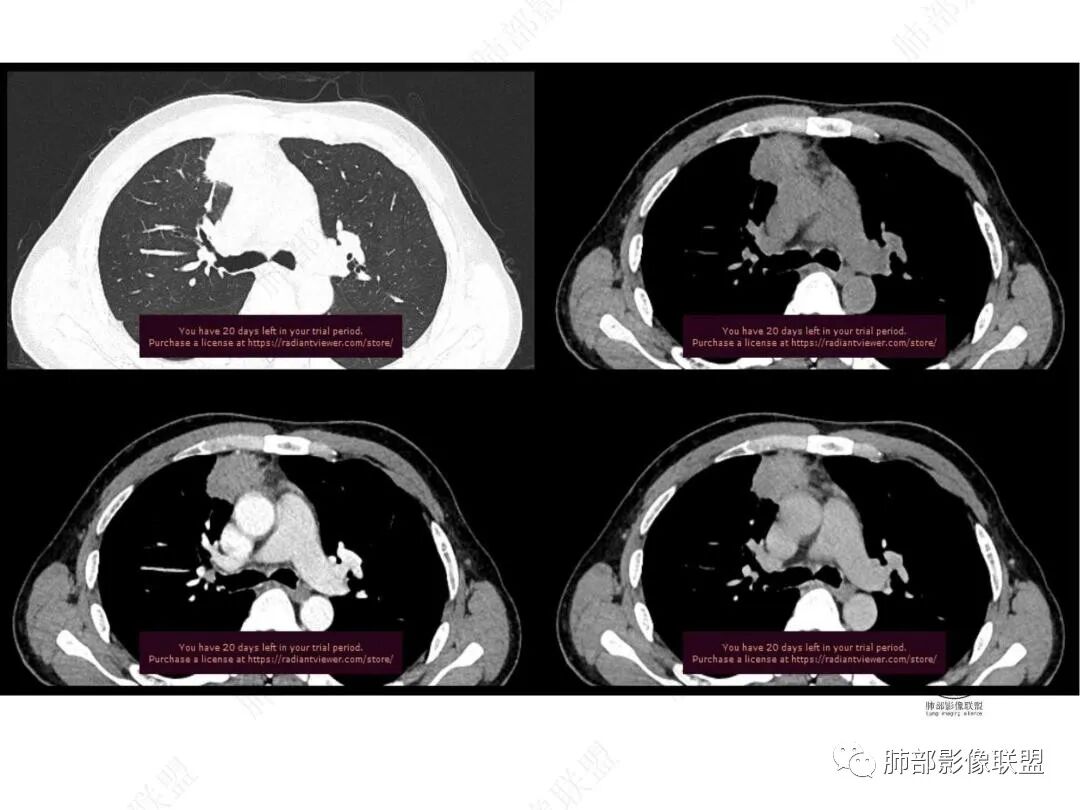

平扫图像

增强图像

右肺上叶前段纵隔旁见团块状影,边缘毛糙,部分直边,支气管进入,管壁增厚,密度均匀,明显强化。考虑炎性病变。纵隔胸膜似有栽桩,腺癌待排。

右肺上叶前段团块影,边缘毛糙,有卫星灶及小空洞,考虑结核。

中年男性,慢性发热3月,白细胞总数及crp升高,右肺上叶实变影,边缘平直为主,似乎均匀强化,血管进入后截断,考虑血管相关性曲霉感染?

中年男性,前纵膈旁团块,边缘平直,周围可见模糊的磨玻璃影,相邻支气管壁增厚,部分支气管进入病灶后阻塞,增强病灶渐进性强化,肝右叶见边缘不清的低密度影,增强渐进性强化。结合实验室检查,总体考虑炎性病变,自免性炎症?血管炎?

中年男性,右前纵隔旁不规则实变影,局部支气管进入后截断,病灶渐进性强化。肝脏右叶低密度灶,边界不清,呈明显渐进性强化。IMT?

右肺上叶纵膈旁团片,边缘毛糙,平直为主,其内见空洞,周围卫星灶,支气管进入阻塞,渐进强化,肝右叶低密度影,边界不清,渐进强化,考虑炎性病变,结核?

男,49,低热3月。胸部CT:右肺上叶前段纵隔旁见团片影,部分边缘毛糙,部分平直、内收,邻近卫星灶、晕征,重建L征?支气管管壁增厚、进入后堵塞;纵隔可见肿大淋巴结;病灶密度较均匀,中度强化。肝脏片状低密度影,边缘模糊。考虑炎性病变,PC?TB?鉴别腺癌。

中年男性,反复低热3月伴近期乏力及右上腹隐痛,白细胞,中性粒及淀粉样蛋白A增高,PCT不高,IGA、IGg增高,类风湿因子增高,未提供IGg4水平,影像改变,左侧肋骨陈旧性骨折(2020年已存在)右上叶前段胸骨旁的胸膜下新发病灶,支气管进入后一段才堵塞,肺动脉进入,走行自然,未见破坏,明显均匀强化,气管及支气管壁有增厚,钙化,纵隔内淋巴结增大,均匀强化,无坏死,纵隔内脂肪混浊,局部强化,肝内低密度灶,延迟强化(肺内病灶,淋巴结、混浊脂肪,肝内病灶强化均一致,且均为延迟强化)。初步考虑:免疫相关性炎症,IGg4相关炎症可能大,依据:IGA、IGg增高(未提供IGg4,可能是故意隐藏了),类风湿因子增高,炎性指标增高,但PCT不高,细菌感染可能就变小,加上病变同时累及肺、纵隔淋巴结,纵隔内脂肪、肝。

右上叶前段胸膜下新发病灶;纵隔淋巴结较前增大

边缘平直,有锯齿状影

支气管进入其中,中近端堵

远端见斑片状高密度影

强化与肌肉类似,纵隔淋巴结强化类似

与胸膜关系:糊墙

1.中年男性,临床发热,症状较轻,中长病程,炎性指标轻度增高。

2.右肺上叶纵隔旁新发实性密度病灶,密度均匀,轻度强化,未见空洞、液化坏死及钙化,血管穿行自如,支气管进入后狭窄截止。灶周磨玻璃影边界不清,病灶未见明显分叶毛刺,平直、轻度收缩、周围偶见结节影,但未见树芽征。注意纵隔胸膜侵入或突入比较明确。纵隔淋巴结轻度增大。